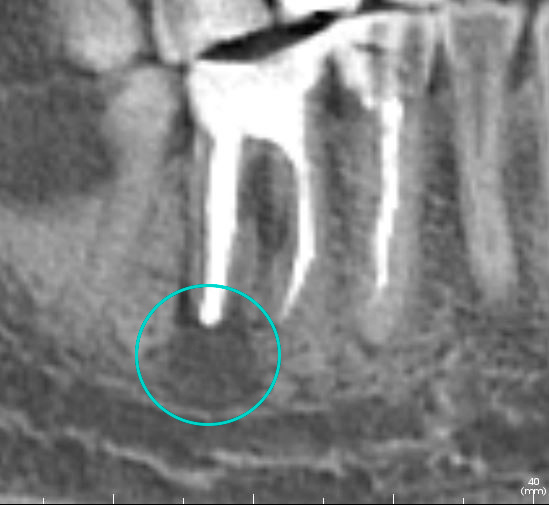

“Киста зуба” – это упрощенное название хронического периодонтита, которая образуется в результате воспаления. Ранее “кисты” часто становились причиной удаления зуба. Сегодня, благодаря современным методам, периодонтит можно лечить, сохраняя зуб. Выбор метода лечения зависит от размера и расположения “кисты”, а также от общего состояния зуба.

— Удалить “кисты” без повреждения зуба

— Вылечить апикальный периодонтит (воспаление на верхушке корней или за верхушкой корней, может возникать вследствие осложненного кариеса)